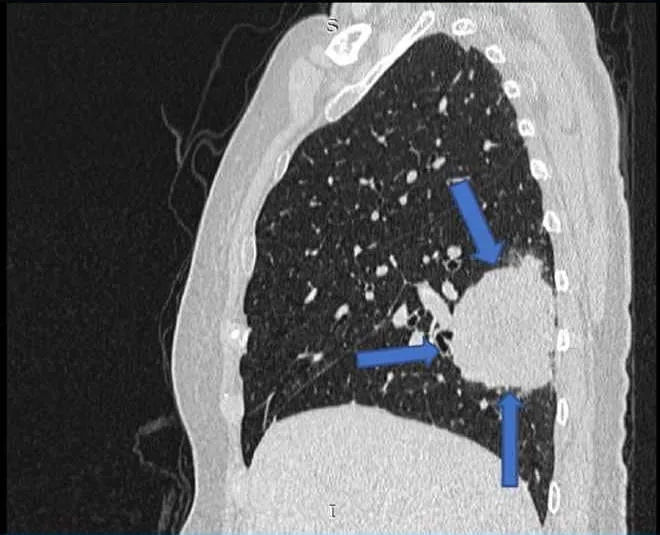

她第一次就诊时的常规胸片(图1)检查偶然发现了右肺肿块。随后的胸部增强计算机断层扫描(CT)(图2)显示肺右下叶后基底段的肺肿块大小为4.7×7.0×7.0 cm(前后×宽度×头尾)。肿块附近也有卫星结节。对肿瘤进行支气管镜活检,组织病理学检查(HPE)结果显示腺癌,证实为原发性肺恶性肿瘤,表皮生长因子受体(EGFR)基因的外显子19缺失。

图2. 胸部计算机断层扫描显示右下叶肿块,周围有卫星结节(箭头)